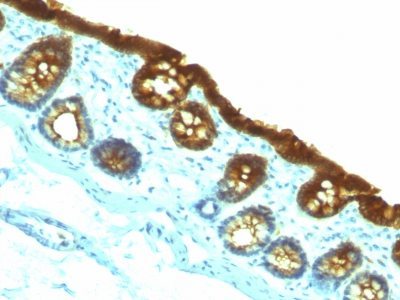

Recognizes a protein of 40 kDa, identified as cytokeratin-19 (CK19), which is expressed in sweat gland, mammary gland ductal and secretory cells, bile ducts, gastrointestinal tract, bladder urothelium, oral epithelia, esophagus, and ectocervical epithelium. Anti-CK19 reacts with a wide variety of epithelial malignancies including adenocarcinomas of the colon, stomach, pancreas, biliary tract, liver, and breast. Perhaps the most useful application is the identification of thyroid carcinoma of the papillary type, although 50%-60% of follicular carcinomas are also labeled. Anti-CK19 is a useful marker for detection of tumor cells in lymph nodes, peripheral blood, bone marrow and breast cancer.